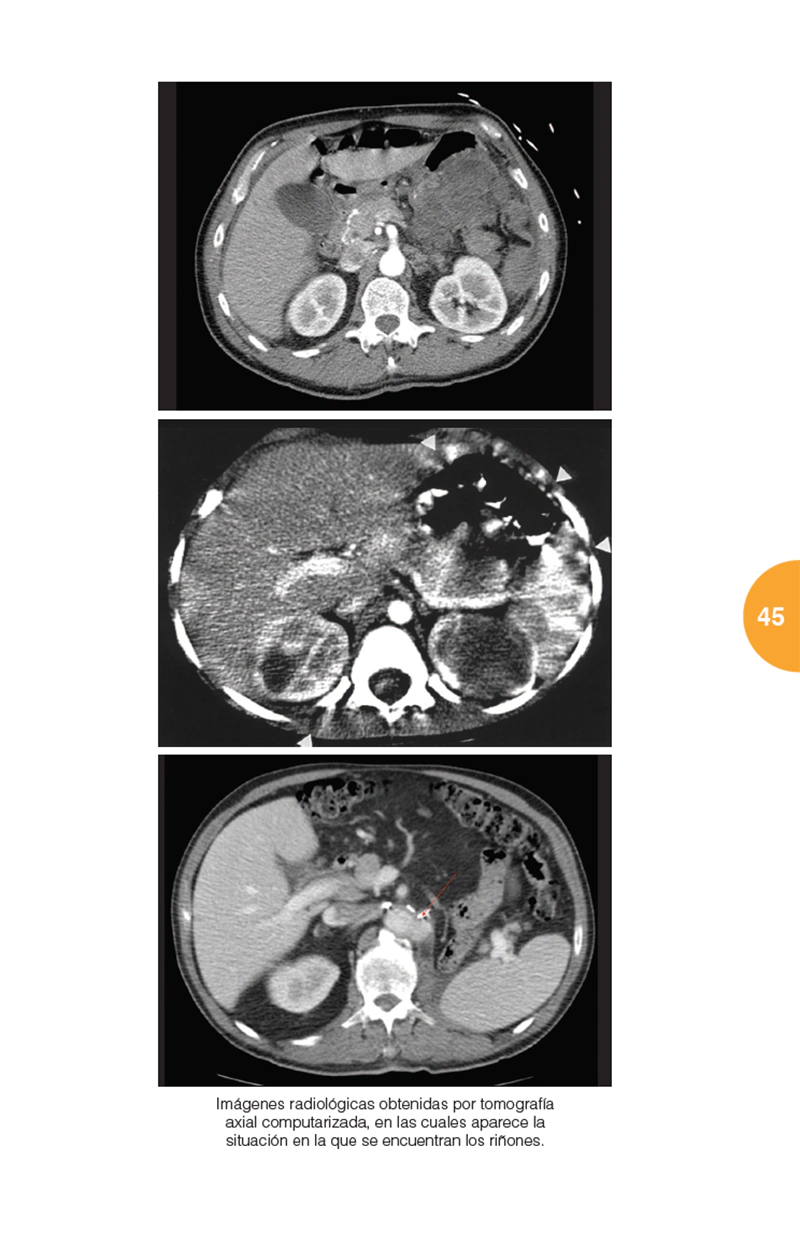

Este libro trata de manera concisa y precisa sobre esta patología y todo aquello que gira en torno a ella: qué es el cáncer de riñón, anatomía patológica, factores de riesgo, cuadro clínico, métodos diagnósticos, tratamiento, cuidados, prevención y un largo etcétera. Tanto el profesional de la medicina, como muchos pacientes y sus familiares encontrarán aquí una información inestimable y cumplida respuesta a mil preguntas que puedan formularse.